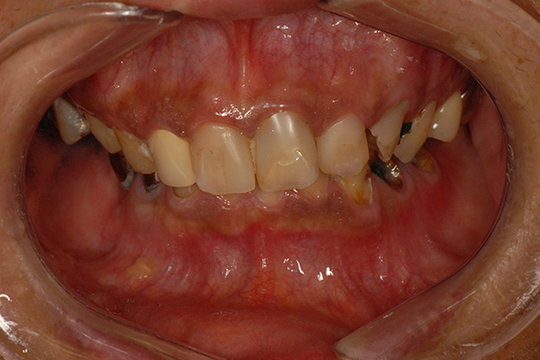

お口の中を5種類のアングルからカメラで撮影します。目視では確認できないところも確認することができます。また、お口の中を患者様ご自身で確認していただくこともできます。